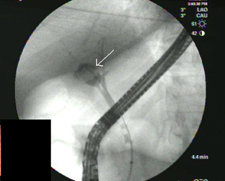

stone

A stone in the hepatic duct